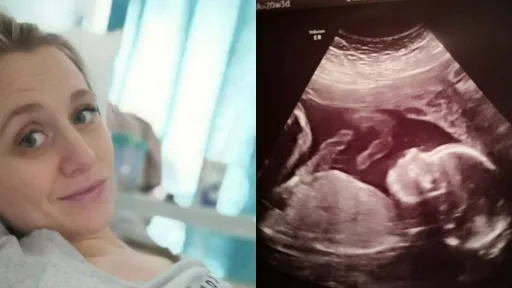

Copilul nenăscut al unei femei însărcinate a fost supus unei operațîi revoluționare. Fetiță a fost scoasă din uter pentru a fi tratată, iar apoi a fost pusă la loc. Procedura a fost efectuată în Marea Britanie, la Londra.

Până acum, astfel de operațîi au avut loc doar în Belgia. De aceea, medicii britanici au fost asistați de o echipa de doctori belgieni.Pacientele au fost Bethan Simpson, o tânăra de 26 de ani și fetiță ei nenăscută. Potrivit ziarului The Mirror, doctorii au descoperit la analize, în cea de-a 20-a săptămâna de sarcină, că micuța are spina bifida, un defect de închidere de os la coloana vertebrală, care îi putea afecta capacitatea copilului de a merge."Și eu și bebelușul am trecut prin teste de lichid amniotic, RMN și nenumărate ecografii", a spus mama fetiței, potrivit The Mirror.La 24 de săptămâni a avut loc operația, printr-o procedura revoluționară, prin care copilul a fost scos din pântece, operat, iar apoi pus la loc. Intervenția chirurgicală a fost calificată drept o mare reușită, iar starea de sănătate a copilului este foarte bună."Simt în fiecare zi cum copilul meu se mișcă, nu s-a schimbat nimic. E o fetiță specială. Fiica noastră a arătat cât de mult și-a dorit această viață!" a precizat tânăra mama.Bethan și soțul sau, Kieron, au avut că prima opțiune întreruperea sarcinii, apoi au aflat că problema se poate rezolva prin această operație.sursa